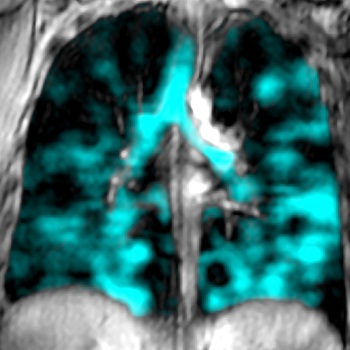

“We had not seen anything like that before,” said Grace Parraga, PhD, professor of Medical Biophysics and Canada Research Chair in Lung Imaging at Schulich Medicine & Dentistry. Parraga, whose research focuses on developing new imaging methods to measure small airway function in asthma and chronic obstructive pulmonary disease (COPD), quickly turned her attention to examining the lungs of vape users. Relying on a specialized MRI method that her team pioneered, research participants inhale a polarized gas that is visible in MRI scans. The team discovered crucial insights into both the destroyed airways and lung alveoli in damaged lung tissue among vape users.

Image of a human lung damaged by vaping. Image of a human lung damaged by vaping.

“Unlike young healthy lungs, young vaper lungs reveal widespread airway inflammation, obstruction and alveolar damage,” said Parraga. “Using an MRI, we could see that the inhaled gas did not fill the lung normally, revealing airways that were choked off and could not ventilate, revealing dark empty lung regions. In young asymptomatic vapers, these abnormalities cannot be detected using chest CT or pulmonary function tests.”

The sensitivity and sophistication of the state of-the-art lung imaging technology developed at Schulich Medicine & Dentistry also enabled Parraga to see the damage done to the tiny air sacs in the lungs and the fine tissue lining the air sacs – a place where an important exchange between oxygen and carbon dioxide happens.

“Lungs have been designed to endure the extreme physical demands of everyday life. Because of this, symptoms don’t present during day-to-day activities until the damage is quite severe,” said Parraga. “The new imaging technology is helping us more deeply understand what’s actually going on.”